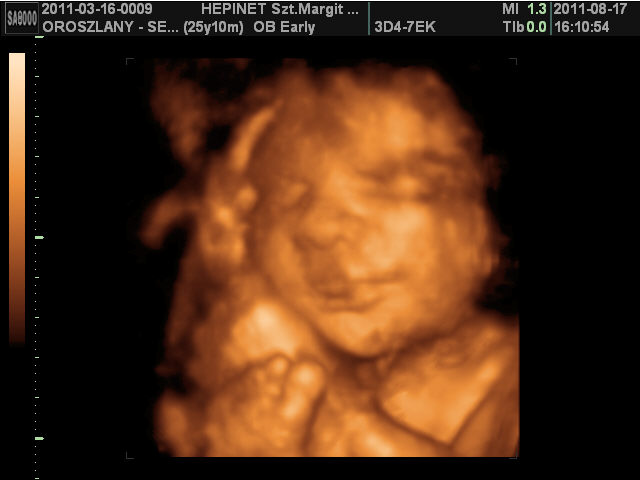

Na, ez volt a Krio, aztán ugye 30. hetin a Hepinetnél voltunk 4D-n, kicsit kíváncsi voltam a kicsim pofikájára :) bár ne lettem volna... :( jól meg lettünk vizsgálva, abban nincs hiba, de szomorú, hogy kifizettem 30 percet, kaptam érte 18-at (mondta a férjem, hogy nagyon hamar eltelt az a 30 perc, de mondtam neki, hogy biztosan csak azért, mert jó volt az UH... sajna nem ), a képek sem lettek olyan jók, pl. a kukifotók alig látszanak (nem azért, mert a gyerek kukkancsát akarom nézegetni, csak ha valakinek megmutatnám, tutira megkérdezné, hogy hová kell a fütyköst odaképzelni?) De az én szívemnek akkor is a 18 perc fáj a legjobban...

Viszont az mókás volt, hogy Samu fiam takarta ám az arcát rendesen, egész felkarral, aztán biztos, ami tuti, a talpát is behúzta a szeme elé, mondtam a néninek, hogy oldalra fordulnék, az szokott segíteni, de nem segített, viszont amikor elkezdtem simogatni a hátát pocakon keresztül, akkor kinyomta, mint itthon is szokta, és kaptunk egy hatalmas vigyort :) De amikor átfordultam a másik oldalra, akkor már morci meg durci volt a kincsem :D (azért itthon is szokott tiltakozni). Teszek fel azért pár képet: